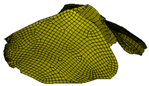

| Cerebrospinal fluid (CSF) | DYNAmore GmbH 2018; Gomez-Gesteira et al., 2012 [32,36] | 1 × 10−9 | – | viscosity coefficient 7 × 10−10 | SPH 191,406 |  |